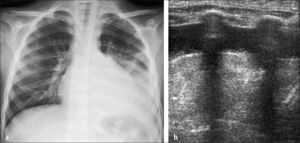

En posición de pies, el derrame se observa radiológicamente como ocupación de los recesos pleuro-diafragmáticos laterales y posteriores cuando es de escasa cuantía y como una opacidad homogénea, que vela el aspecto inferior del hemitórax, con un contorno que asciende lateralmente en proyección frontal dando la clásica incurvación con aspecto de menisco en relación al margen superior del derrame (Figura 6). Si este contenido líquido se encuentra libre en el espacio pleural, se movilizará con los cambios de posición y así por ejemplo, en decúbito se distribuirá homogéneamente en el aspecto posterior del espacio pleural observándose radiológicamente como un hemitórax más denso que el contralateral (4).

Puede sospecharse en Rx simple, cuando el compromiso pleural no pre senta el aspecto descrito previamente para el derrame libre, especialmente si se observa un aspecto convexo localizado que sugiere loculación. En estos casos el estudio puede complementarse con US efectuada con transductor de alta resolución. Ramnath (11) clasificó los derrames en “bajo grado” cuando están constituidos por líquido anecogénico (Figura 9), sin septos y “alto grado” cuando muestran imágenes de septos, lóculos o sedimento, signos altamente sugerentes de derrame pleural complicado (Figura 10).